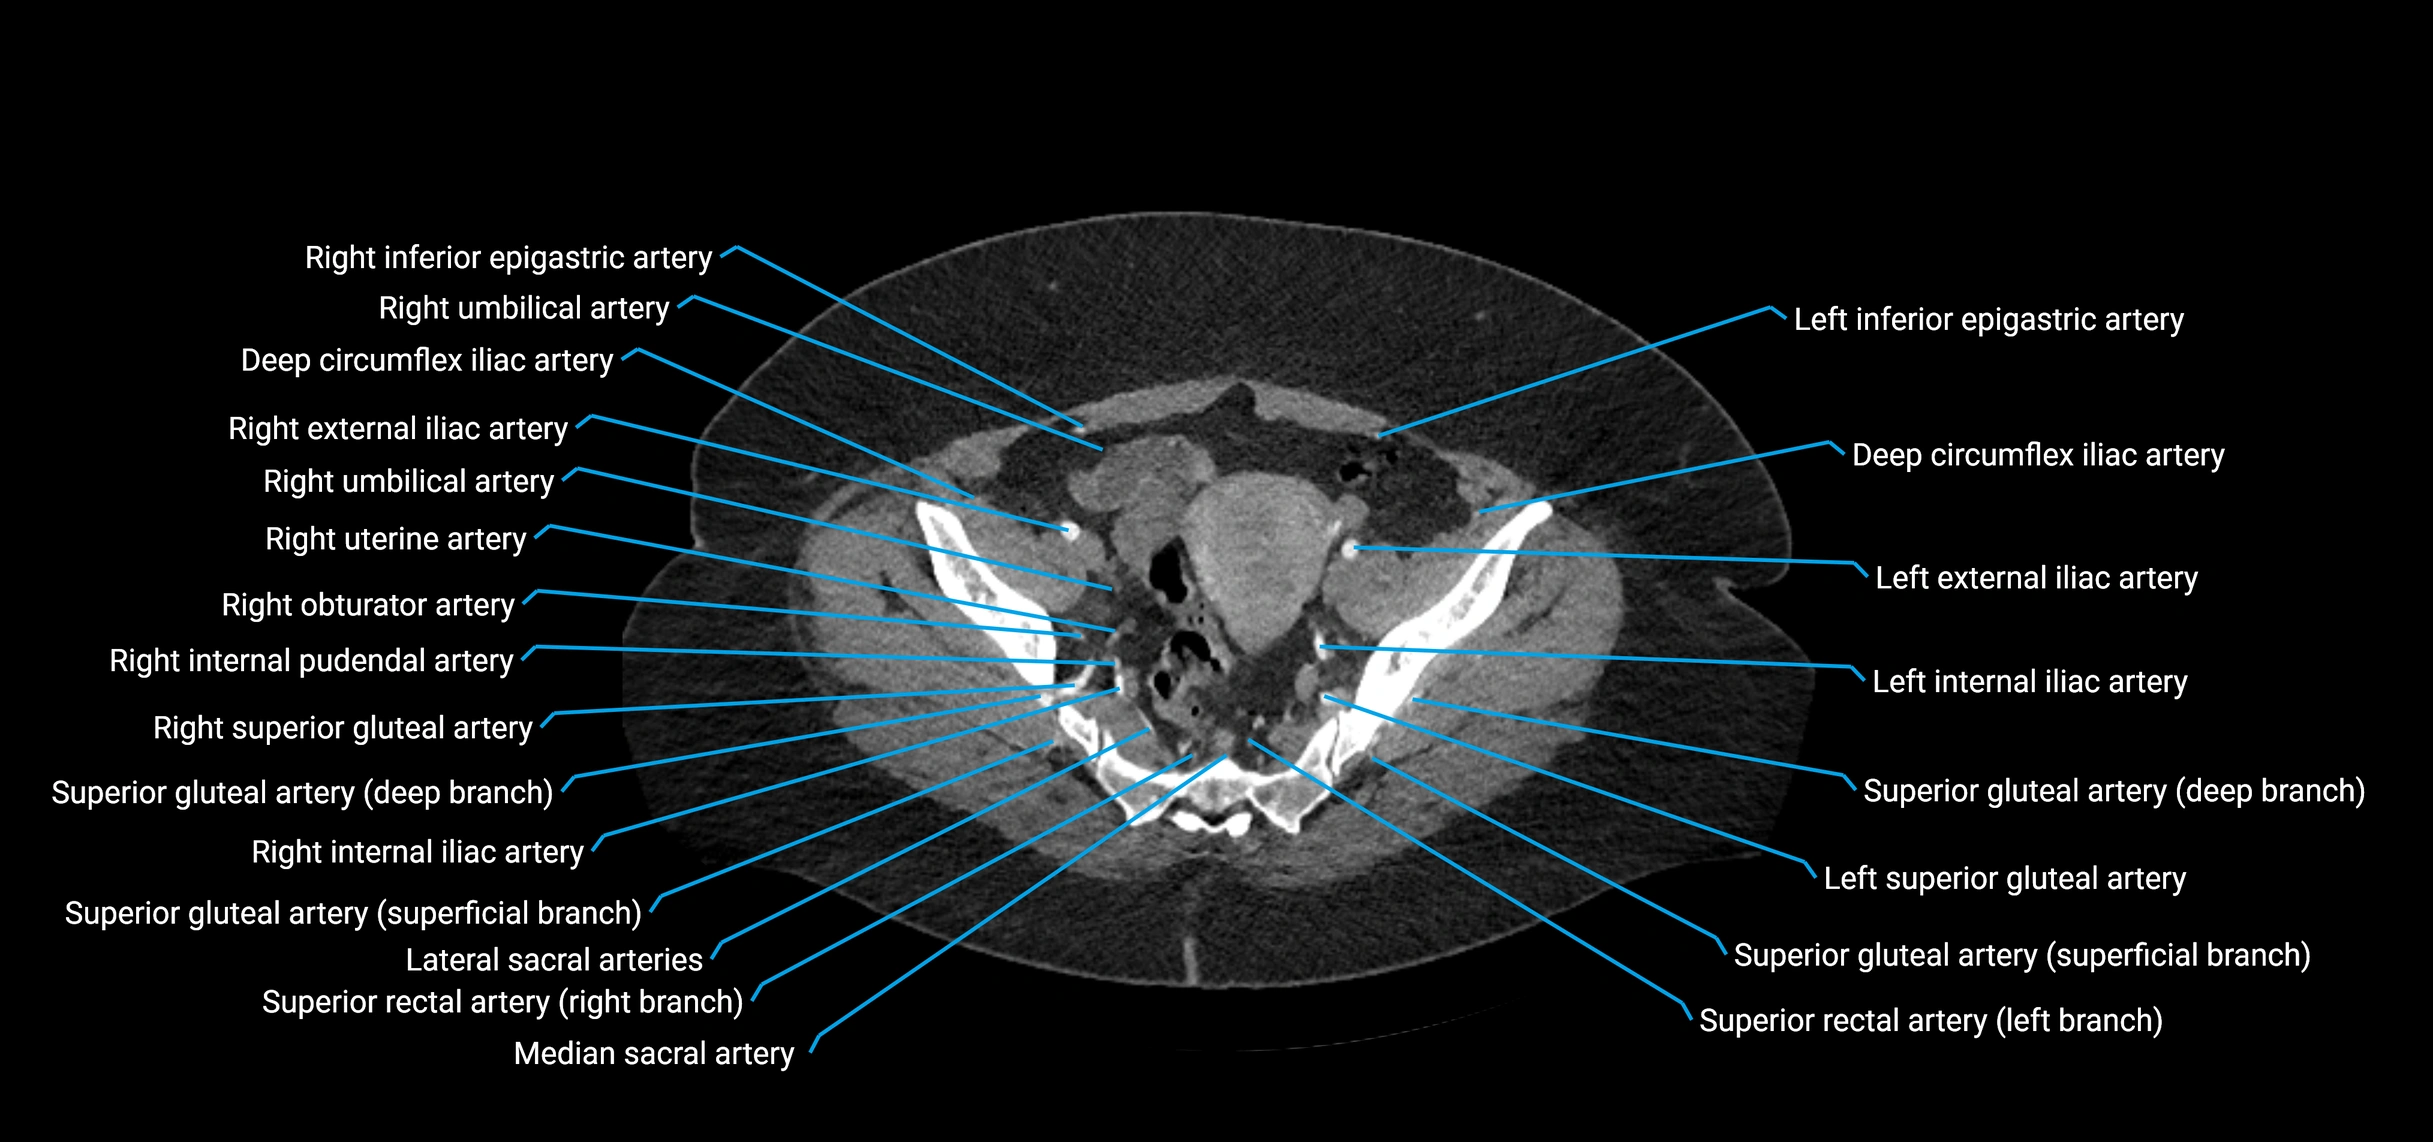

Contrast-enhanced CT (CTA):

• Gold standard for abdominal aortic imaging

• Provides excellent detail of lumen, wall, aneurysm, thrombus, and branch vessels

• Multiplanar and 3D reconstructions help in aneurysm measurement, stent graft planning, and dissection evaluation

• Detects acute rupture, traumatic injury, or occlusion with high sensitivity